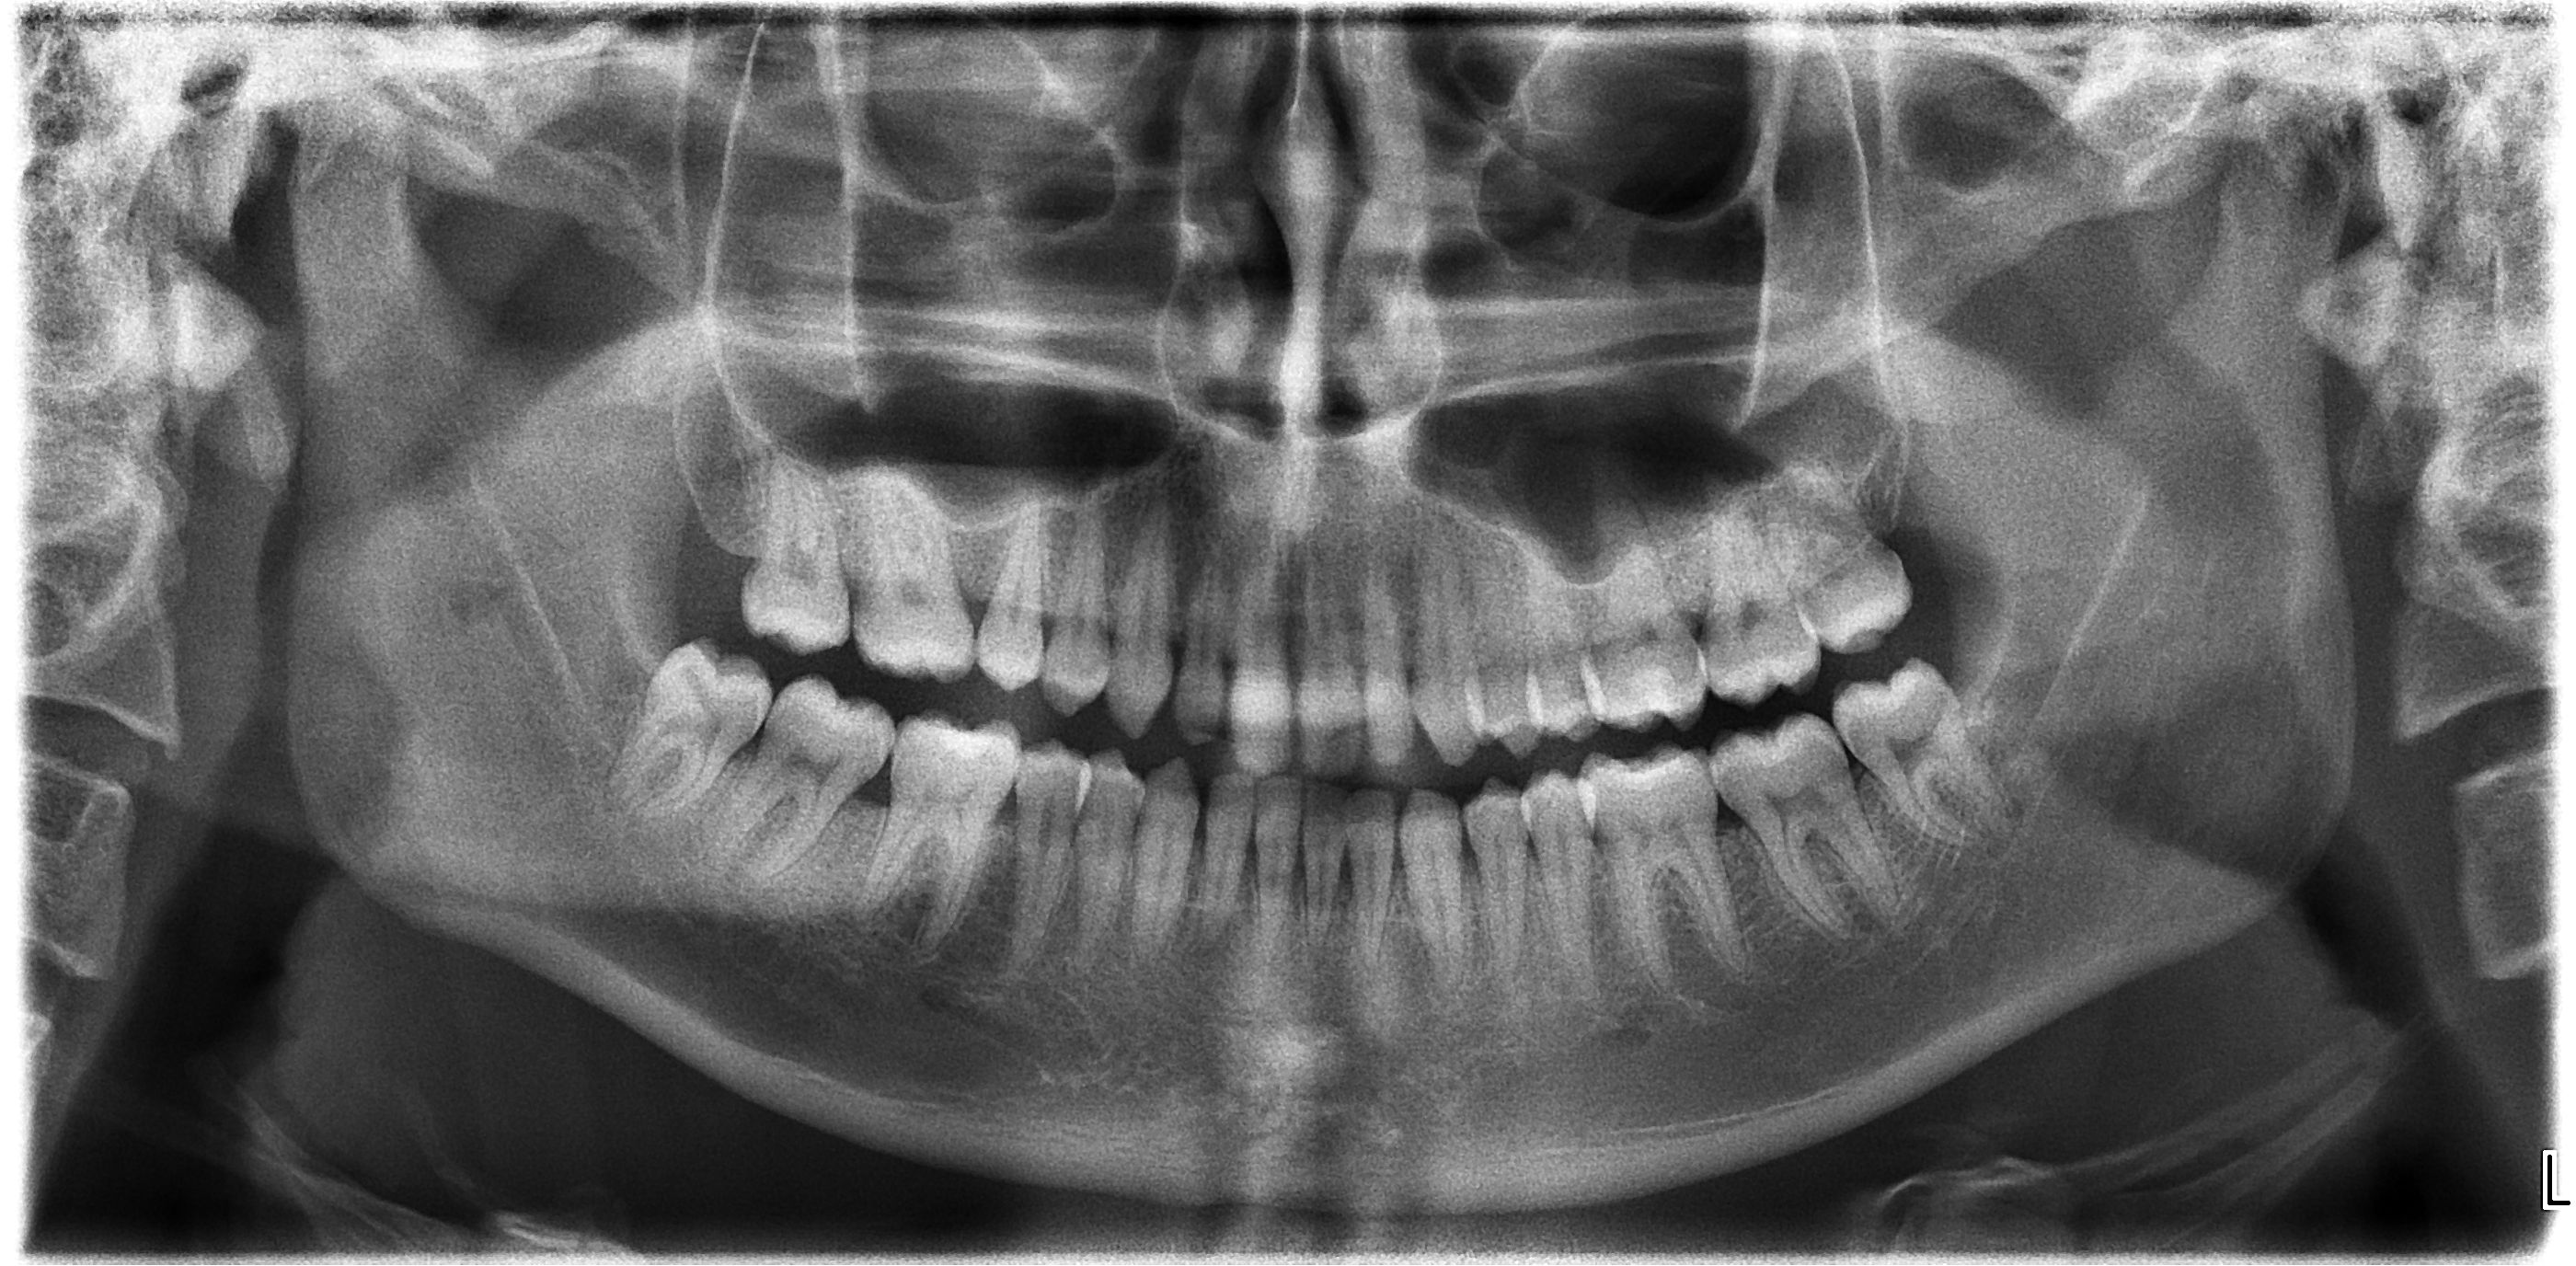

Molti mesi fà mi recai da uno specialista in ortodonzia perchè volevo correggere i miei denti storti

Molti mesi fà mi recai da uno specialista in ortodonzia perchè volevo correggere i miei denti storti (incisivi centrali superiori e inferiori sporgenti e piccoli diastemi) dopo aver effettuato una lastra il mio dentista ha deciso che non era il caso di mettere apparecchi ortodontici, per il seguente motivo: 'Dopo aver valutato la